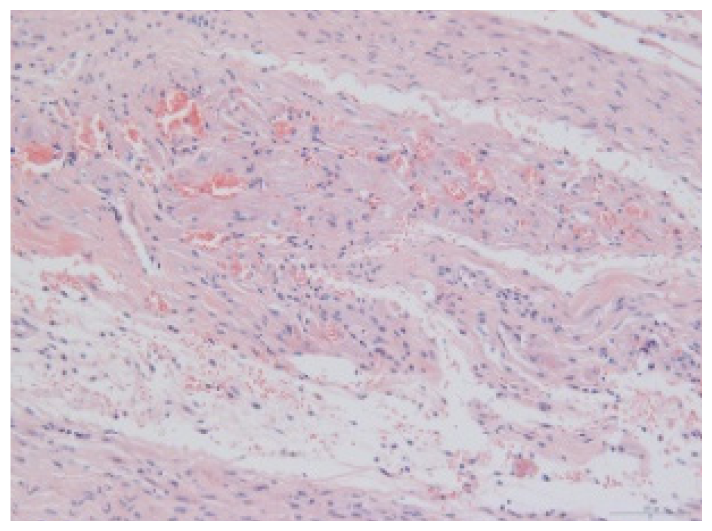

2.1.6. CoPP Treatment Diminished Infarct and Peri-Infarct Area in ISHR Model

2.1.7. CoPP Treatment Inhibited Ventricular Remodeling of Post-Infarction in SHR

| Groups | Masson (macroscopic) | Masson (×200) | Infarct area (HE ×200) | Peri-infarct area (HE ×200) |

|---|---|---|---|---|

| WN | ![]() | ![]() | ![]() | |

| SMN | ![]() | ![]() | ![]() | ![]() |

| SMC | ![]() | ![]() | ![]() | ![]() |

| SMS | ![]() | ![]() | ![]() | ![]() |